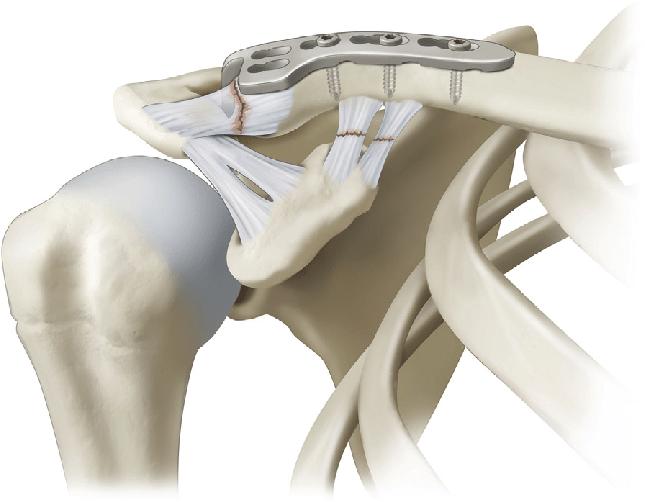

| Хирургическое лечение: при частых рецидивах вывиха или значительном повреждении связок. | Обсудить с врачом показания к операции. | |

Каждый должен осознавать, что вывих плечевого сустава может быть опасен также из-за растяжения плечевой капсулы. В некоторых случаях может потребоваться хирургическое вмешательство. Поэтому крайне важно пройти диагностические процедуры перед тем, как проводить вправление.

В некоторых случаях последствия могут быть настолько серьезными, что для устранения вывиха потребуется хирургическое вмешательство и длительный процесс восстановления поврежденных тканей. То же самое касается и внутренних переломов – иногда необходимо устанавливать специальный протез.

К сожалению, в некоторых случаях вывих плечевого сустава повторяется вновь. Это может говорить о том, что суставная капсула внутри плеча сильно повреждена, поэтому пациент должен будет сделать томографию, чтобы определиться с дальнейшем лечением. В некоторых случаях будет предложено хирургическое вмешательство и искусственное восстановление сустава. Опасаться такой операции не стоит, поскольку она не несет угрозы жизни больному.

Кроме того, такая операция также поможет восстановить функцию связок и мускулатуры. Ведь очень часто вывихи продолжают происходить только потому, что после неправильного вправления ткани начали постепенно терять свою силу. использование специального мышечного каркаса позволит восстановить их прежнее состояние, что предотвратит риск возникновения вывихов в будущем. Ведь сильные мышцы – залог крепких суставов.